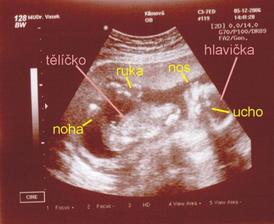

Nedovedete si představit to velké štěstí...které nás potkalo, je to prostě náš ZÁZRAK. Teď jsem sice plná obav a strachu o miminko, i nějaké komplikace se vyskytli, ale snad všechno dobře dopadne, a nám se v květnu, rok po naší svatbě, narodí krásné a zdravé miminko...náš malý - Velký Zázrak.